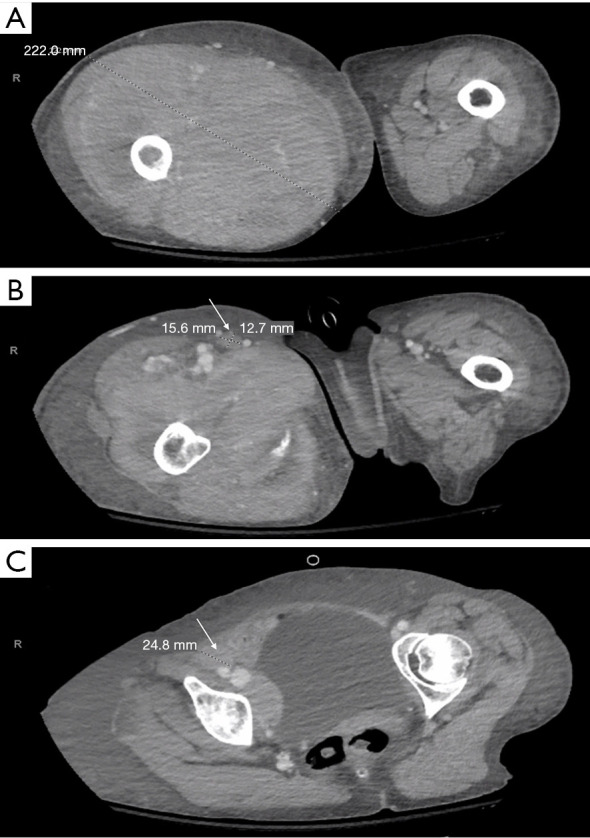

Case description: A 68-year-old woman presented to the emergency room with increased swelling and pain in her right leg, was subsequently diagnosed with right thigh compartment syndrome, and underwent urgent fasciotomy followed by repeat debridement in the medical wound closure. Additionally, the patient was found to have inguinal and external iliac lymphadenopathy along with deep vein thrombosis (DVT). Her past medical history included human immunodeficiency virus (HIV) infection, which was well-controlled with bictegravir, emtricitabine, and tenofovir alafenamide. Excisional biopsy of the right thigh muscle and fluorescence in situ hybridization (FISH) analysis confirmed the diagnosis of high-grade B-cell lymphoma with MYC and BCL2 gene rearrangements arising in the setting of immunodeficiency/dysregulation (lymphoma associated with HIV infection). Despite aggressive medical management in the intensive care unit, the patient succumbed to the disease and ultimately died from sepsis and hemorrhagic shock.